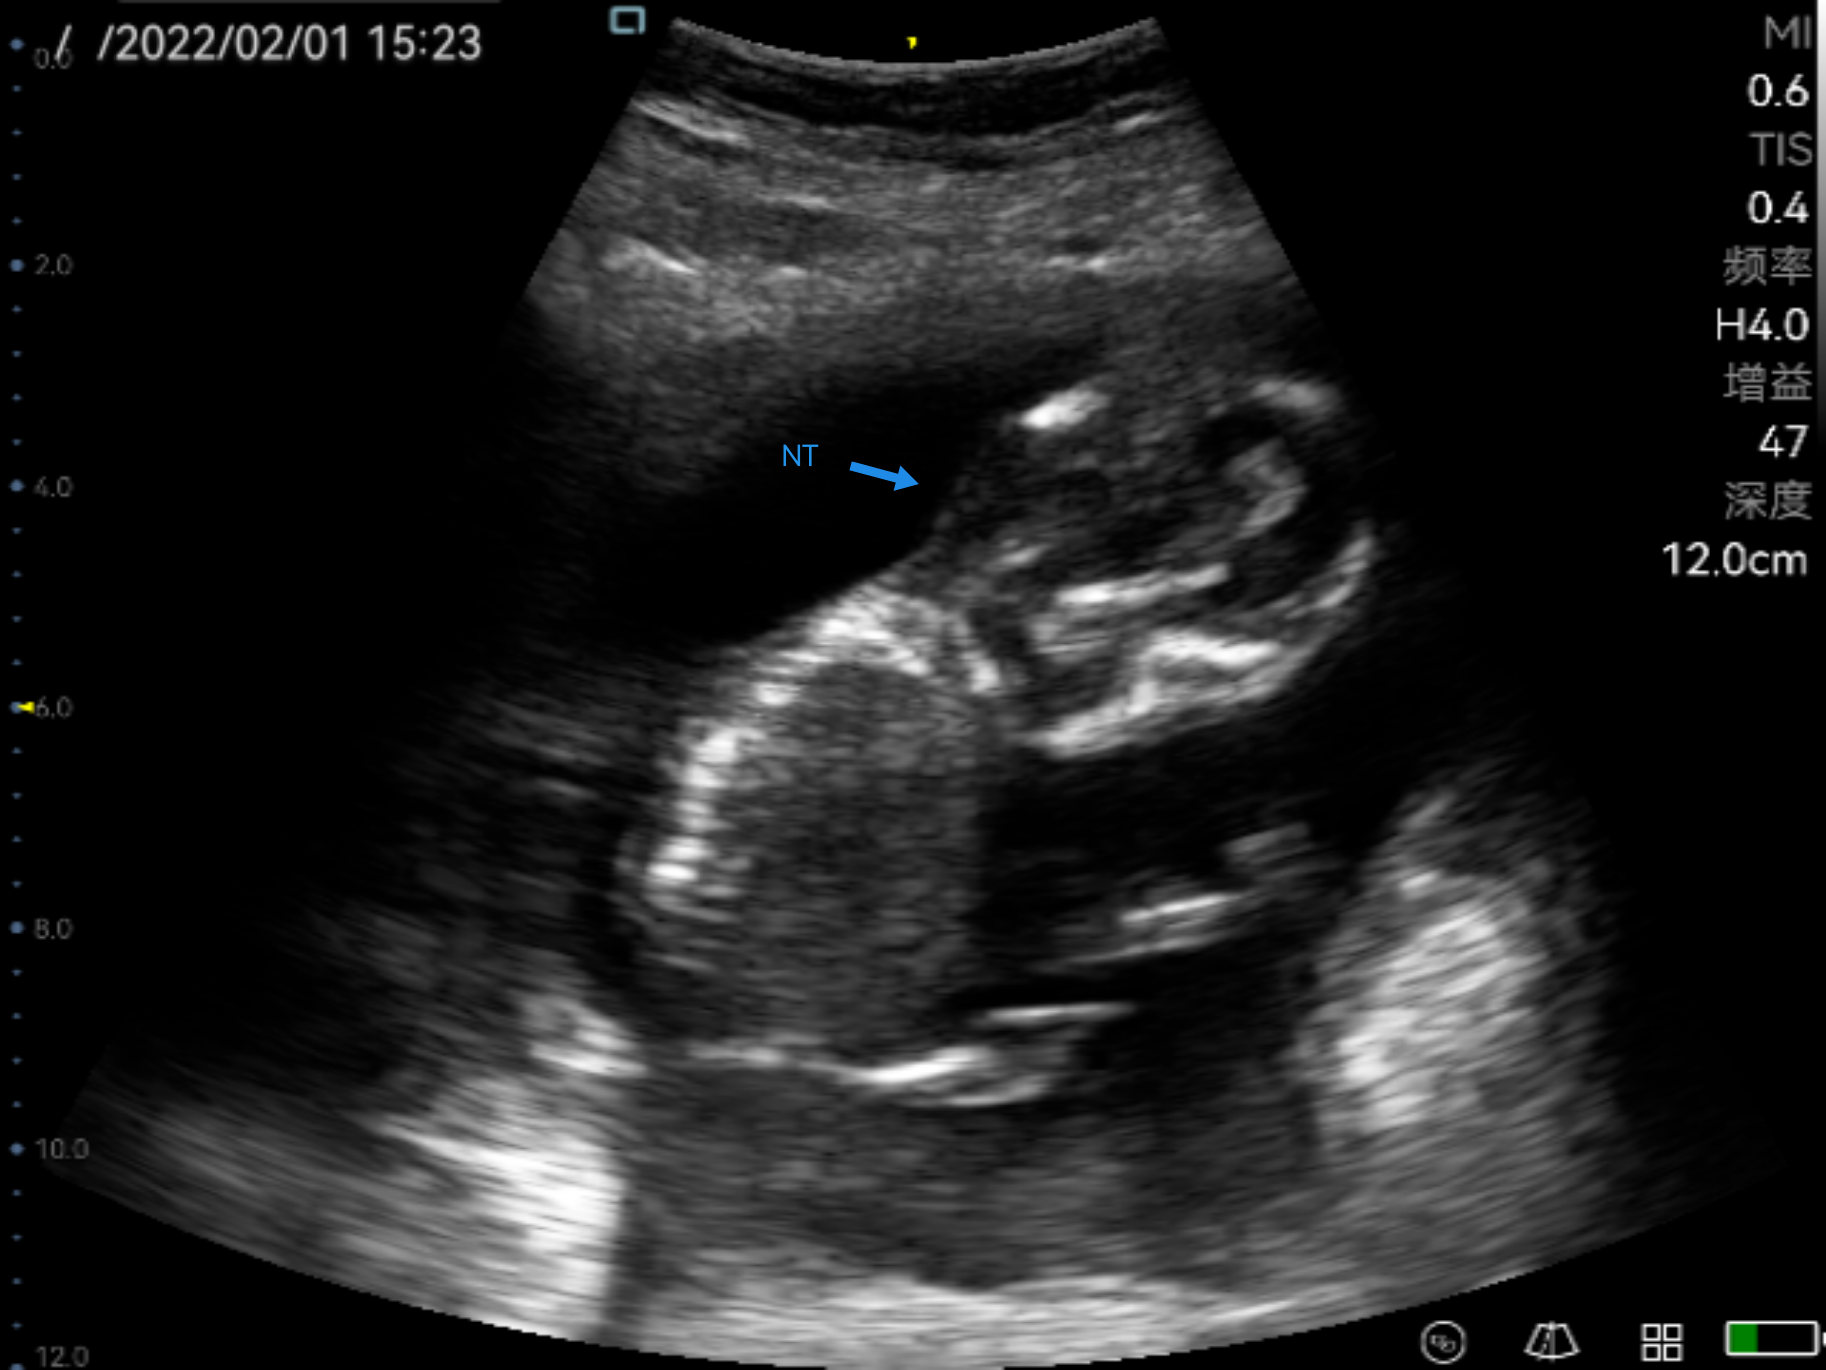

Obstetric ultrasonography is one of the routine prenatal examination items. The ultrasonic diagnostic instrument is used to scan various sections of the human body. According to the amplitude of the echo signal, real-time imaging is performed on the monitor, so it can detect the uterine appendages and the fetus. Through the biological measurement of the fetal head, abdomen, long bones, etc., the gestational age and the size of the fetus can be estimated. Through the observation of real-time dynamic ultrasound images, it is possible to detect whether the fetus has structural abnormalities, determine the degree of fetal malformation, evaluate the prognosis, whether clinical treatment is required to preserve fetal survival. For pregnant women with no abnormal performance within ten weeks, no ultrasound examination is required. For older and high-risk pregnancy, obstetric ultrasound examination must be performed regardless of the gestational age, which not only ensures the safety of the fetus, but also prepares for delivery. Ultrasound is widely used in obstetrics because of its non-radiation, simple operation, flexibility and convenience, high resolution, and moderate examination price.

The practical application of P50 in obstetrics

Perioperative period is helpful for doctors to assess the real-time labor processes of the placenta, amniotic fluid etc.

Ultrasonography in early, middle and third trimester, obstetric Doppler ultrasound, normal twin pregnancy, ultrasound diagnosis of common fetal structural malformations, twin pregnancy complications, abnormal pregnancy, abnormal pregnancy appendages, real-time monitoring of midwifery, etc.